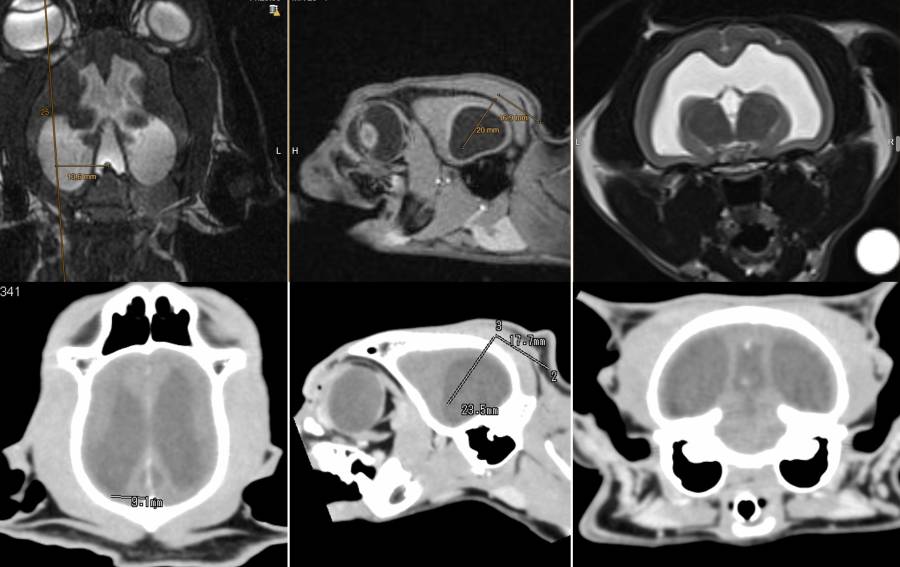

- US bei offenen Fontanellen

- CT / MRT

- vergrößerte Liquorräume und Anzeichen des Überdruckes (Kleinhirnherniation)

- nicht alle Patienten mit größeren Ventrikel haben einen Hydrocephalus

- Ventrikelasymmetrie ist häufig (38%)